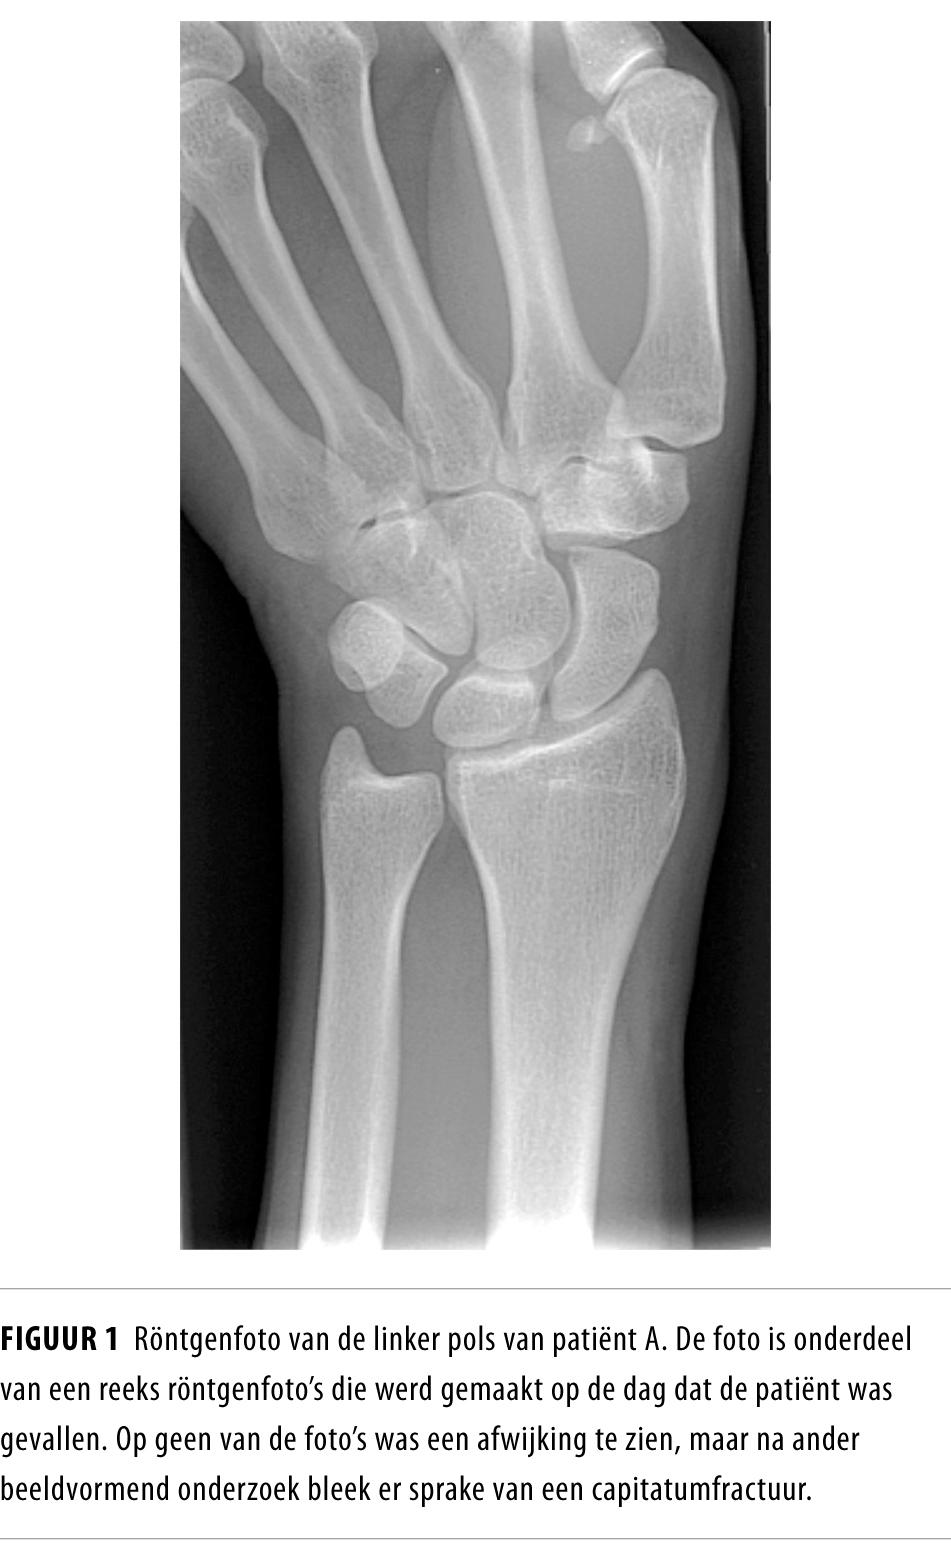

Wij presenteren een patiënt met een polstrauma die werd opgevangen op de Spoedeisende Hulp. Het traumamechanisme en de klinische bevindingen wezen sterk op een scafoïdfractuur. Op de röntgenfoto’s was geen afwijking te zien, maar toch werd de fractuur behandeld met gips. Op de CT-scan bleek later inderdaad een niet-gedisloceerde fractuur in het os capitatum aanwezig. Deze diagnose werd enige dagen later bevestigd met botscintigrafie. De patiënt is restloos genezen.

Capitatumfracturen zijn ernstige carpale letsels, die net zo agressief behandeld moeten worden als scafoïdfracturen. Met conventioneel röntgenonderzoek kan een polsfractuur niet worden uitgesloten; bij twijfel is het aan te raden laagdrempelig beeldvormend onderzoek (bijvoorbeeld CT of MRI) te verrichten.